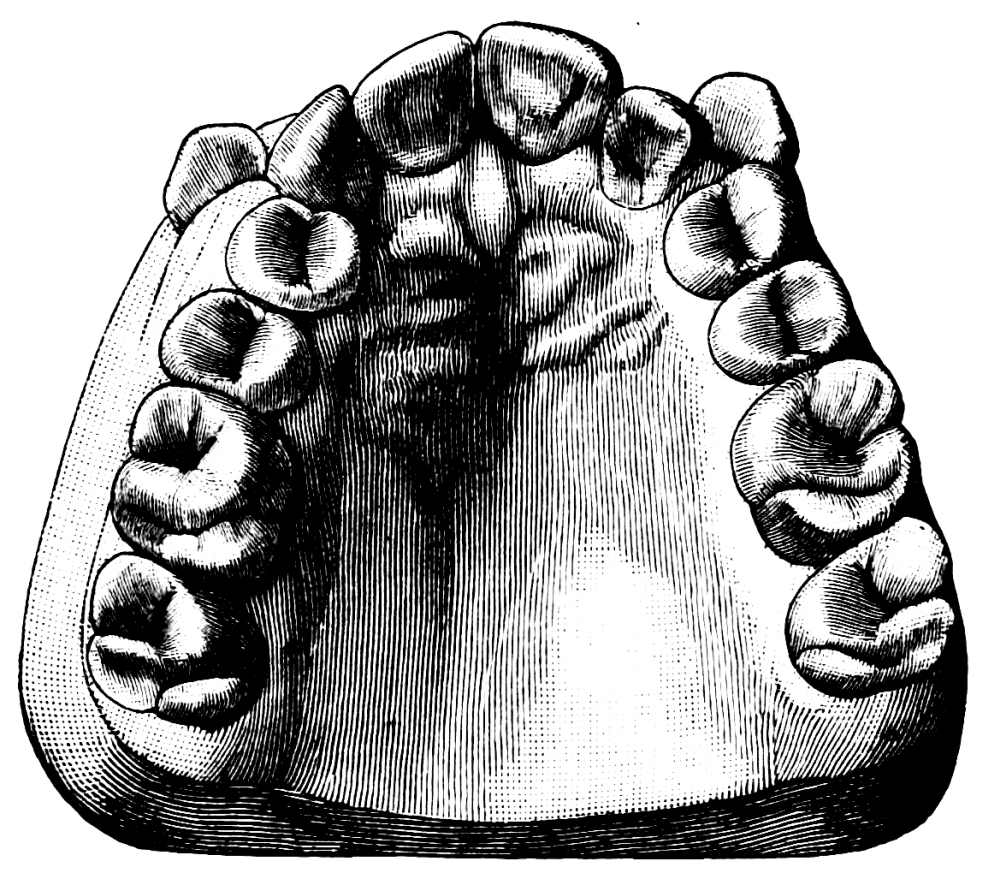

Fig. 28.

(d) Lower Molars.—Lower molars have two roots, placed anteriorly and posteriorly. The roots are much flattened and have a tendency to curve backwards, this being well marked in the second and especially so in the third molar; a fusion of the two roots is at times met with in the second and frequently in the third molar. A section of a lower molar at the neck shows both the buccal and lingual aspects to be composed of two segments of a circle touching each other at one extremity; the anterior segment being slightly the larger (fig. 28). Each blade of the forceps used for these teeth should possess two grooves,{36}

Fig. 29.   Fig. 30.

separated by a projection which fits into the division between the anterior and posterior roots; for all practical purposes the blades may be made of the same size, so that one instrument will suffice for both sides of the jaw. The instrument best adapted for the removal of these teeth is shown in fig. 29, though some operators prefer the shape illustrated in fig. 30. The advantages of the{37} former over the latter may be briefly summed up as follows:

(1) A clear view of the tooth and its surroundings can be obtained during the whole period of removal.

(2) Force can be applied with greater advantage.

(3) The alveolus can be easily embraced by the fingers, or by the finger and thumb of the left hand.

(4) In removing the tooth from the socket a slight backward movement can be employed.

One disadvantage of shape fig. 29 is that it is difficult to employ much inward movement, and therefore, for teeth lying inwards, namely, with the crown directed towards the tongue, hawk’s-bill-shaped forceps cannot easily be used.

Another disadvantage is that the extent of inward movement is limited by the proximity of the upper teeth, and in case of trismus it is often better to use straight forceps (fig. 30). In cases where there are also much swelling and rigidity of the cheek the straight forceps cause less inconvenience to the patient.